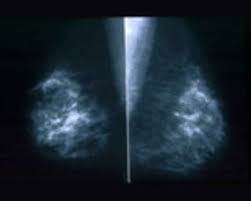

How Long Does It Take For Mammogram Results : When to get a screening mammogram?. If you have breast implants, the mammography will take approximately 30 minutes, because it takes more time to make sure clear images are taken. Sometimes extra views are taken, which will take longer. How long do i have to wait before getting mammogram results? Diagnostic mammograms are usually interpreted in the same day, unless old films are needed. What not to do before a mammogram?

Sep 22, 2020 · it will take a few days, maybe even more than a week, for you to find out the results. How long do i have to wait to get an ultrasound? All in all, you should have your results within a week or two of having a. May 27, 2021 · the mammogram process takes about 15 minutes, and people should expect their results within 2 weeks. Diagnostic mammograms are usually interpreted in the same day, unless old films are needed. So was my reaction when the technician told me to expect a postcard about my test results in 10 to 12 days. Quite often the most prudent measure for a very 'low risk' finding is simply to 'observe' the suspicious lesion on subsequent mammograms, at intervals ranging from six months to a year. When to get a screening mammogram? If you have breast implants, the mammography will take approximately 30 minutes, because it takes more time to make sure clear images are taken. Apr 17, 2020 · in most cases, your doctor will mail you the results, which means it could take a few days to receive the results. Jan 06, 2016 · to set your mind at ease, i will tell you right now that my mammogram was negative. Medically reviewed by carolyn kay, m.d. If the results are negative or benign, that means no cancer was found.